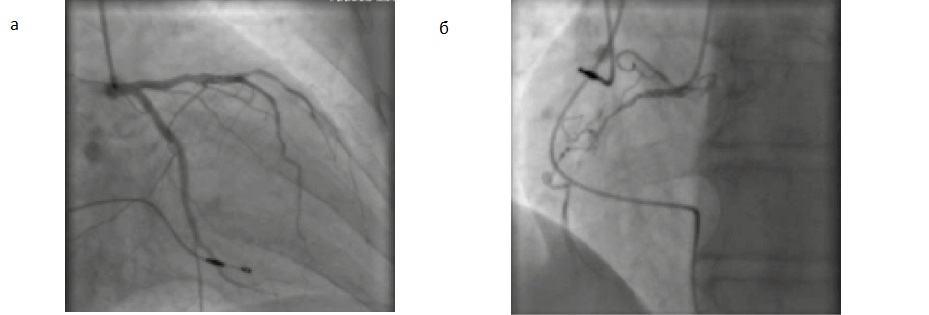

КАГ. Тип кровоснабжения правый. Ствол левой коронарной артерии (ЛКА) не изменен. Передняя нисходящая артерия, диагональная артерия имеют неровные контуры. Ранее установленный стент в огибающей артерии проходим без признаков рестеноза. Правая коронарная артерия диффузно изменена, в средней трети окклюзирована (рис. 3).

Рис. 3. Предоперационная КАГ: а – ЛКА, б – правая коронарная артерия.